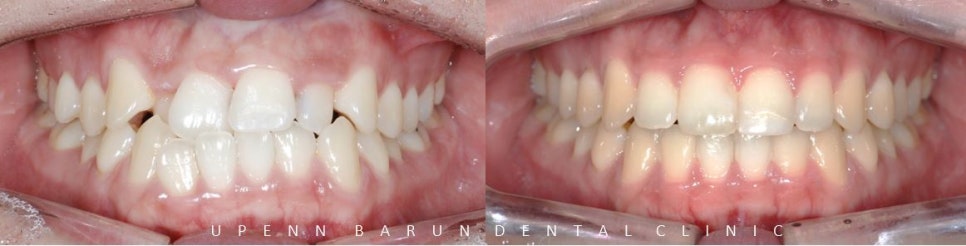

위, 아래 앞니가 정확히 맞물리지 않았던 이전과는 달리

입천장쪽으로 쏙 들어가 있던 위앞니가 제 자리를 찾으며

치아들이 가지런히 펴졌는데요 ^^

앞니의 높이와 모양이 불규칙하고

잇몸선이 삐뚤삐뚤해 치아의 잇몸 라인이 고르지 못했던 이전과는 달리

통증이 적은 레이저를 이용한 간단한 잇몸 성형을 통해 과도한 치은의 노출을 개선시켜 웃을때 가지런하며 시원한 느낌을 받을 수 있습니다 ^^

윗 앞니들의 아랫부분을 연결한 곡선이 아랫입술의 곡선과 평행을 이루어

예쁜 Smile Arc를 그립니다. 이것이 웃을때 더 예쁜 데이몬교정의 특징, Damon Smile 입니다.